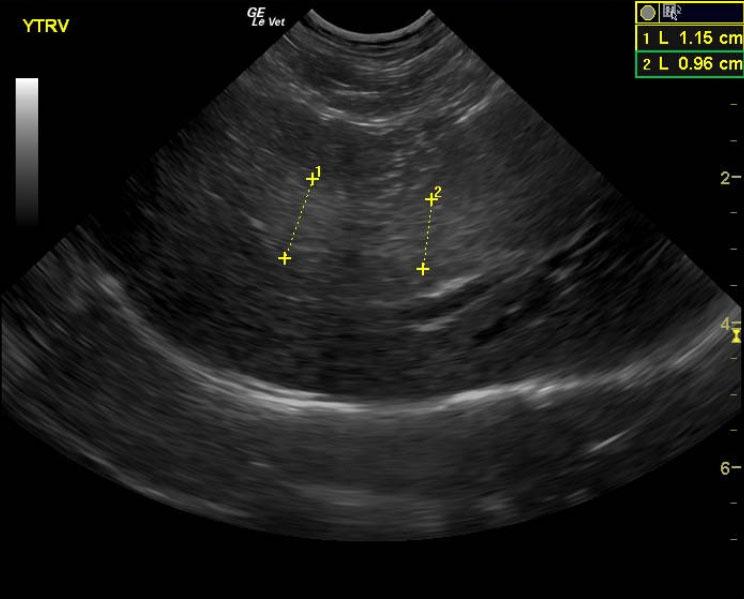

A 15-year-old MN DMH cat was presented for chronic diarrhea, hyperthyroid, dehydration, otitis externa, and periodontal disease. The CBC was markedly normal with blood chemistry revealing an elevated ALT (154,) elevated SAP (109,) hyperT4 (>10,). An IDEXX feline diarrhea panel was negative for virus, parasites, & bacteria.